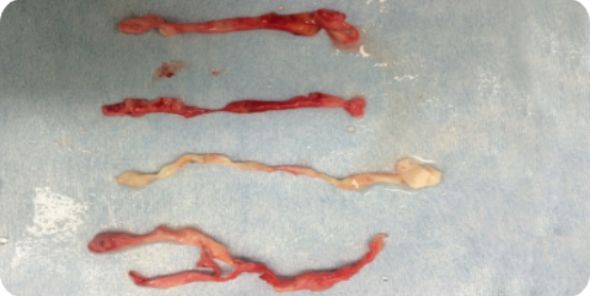

B

静脈の逆流を止める!

静脈瘤の原因となっていた静脈を抜去

- ※画像の無断転用は禁止です